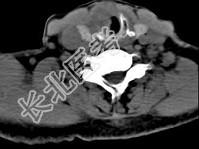

- 单项选择题男,62岁, 声音嘶哑1年余,CT图片如下, 最可能的诊断是 ( )

A、甲状腺癌

B、声门下喉癌伴右颈部淋巴结转移

C、喉结核伴右颈部淋巴结肿大

D、喉转移瘤

E、喉息肉